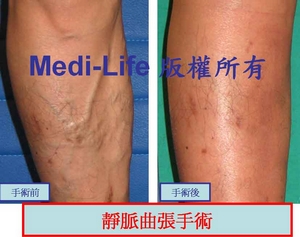

在進行全腿雕塑或蘿蔔腿手術的時候, 可以利用 TIPP (transilluminated powered phlebectomy, 經皮透視性、動力輔助式顯微手術) 或 顯微靜脈切除 特殊器械, 將青筋浮現的靜脈問題一併解決. 不用分好幾次療程-- [一次解決方案], 不會有另外的恢復期, 等於同時解決多項問題!! 更神奇的是恢復期不會加長, 而是同樣的時間處理掉多重問題.

即使嚴重到靜脈曲張亦是可以輕易解決.

即使嚴重到靜脈曲張亦是可以輕易解決.

另一個案例: 手術後三週照片

另一個案例: 手術後三週照片